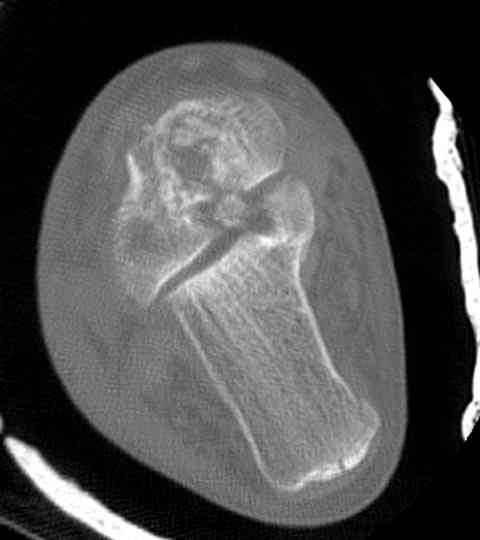

а основании двух видов ренгенограмм невозможно радикально решить о необходимости открытой репозиции или первичного артродеза.

Для оценки состояния нужны дополнительные исследования, например Canale или Broden ренгенограммы и Компьютерная томография.

При переломах тарана всегда имеется риск AVN, а классификация Hawkins поможет разобраться с предполагаемыми осложнениями.

Если в первом типе, когда перелом шейки без смещения, тогда AVN менее 10%, при втором типе когда имеется смещение и вывих тарана в субталарном сочленении меньше 40%, а при типе III когда смещение в голеностопном и субталарном суставах - около 90% и в типе IV, когда происходит полный вывих, риск AVN достигает 100%.

На ренгенограмме не уловил многоскольчатость тарана, чтобы доказать, конечно, можно было исследовать на КТ, потом КТ дает ориентацию фрагментов.

Два фрагмента суставной поверхности тарана можно восстановить боковой компрессией шурупами и дополнительно костная пластика.